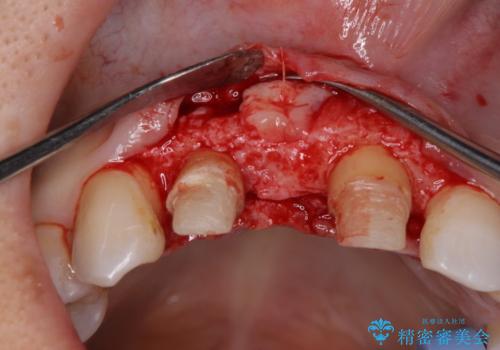

現在装着されているブリッジを除去したところ、歯ぐきよりも上に存在する歯質(縁上歯質)が少なく、土台の形態の悪さや不適合などさまざまな問題があります。

根管治療を行ったのち、歯周外科を行うことで、欠損部の歯ぐきの厚みを出し、縁上歯質を獲得することで、長期的な予後の見込めるブリッジを製作できる環境を整備していきます。